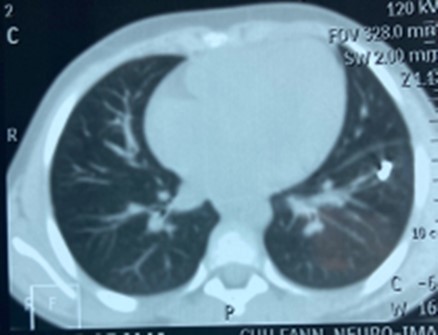

AD, aged 10, with no particular pathological history, was referred to us for the management of a post-traumatic intrapulmonary foreign body. The traumatism would have occurred one month earlier, during a playful accident. He would have received from his brother, at the level of the left hemithorax, a blow with the metal tail of a comb. The latter would then have been torn off by the child but without the tail. This would have caused a minimal wound, associated with an intense chest pain, without dyspnea, or cough, justifying local care and treatment with analgesics. The incident was withheld from parents. On admission, there was a punctiform scar in the 2nd left intercostal space, about 5 cm from the sternal border. The pulmonary fields were free. The rest of the exam was normal. The biological results were normal. A first chest x-ray showed a metal rod, oblique downwards, backwards and inwards, going from the 5th to the 11th left costal arch (Figure 1). The computed tomography scan of the chest showed the metal rod in the lung parenchyma. It was approximately 105 mm long and stayed away from the heart and the great vessels. There was no pulmonary parenchymal abnormality, pleural effusion or obvious bone lesion (Figure 2). Two subsequent X-rays showed its migration downwards, inwards and backwards with an upper pole sitting opposite the posterior arch of the 8th rib. A left posterolateral thoracotomy approach allowed the removal of the metal rod lodged in the lower lobe of the lung (Figure 3). The postoperative period was unremarkable. The ablation of the drains was carried out on the5th postoperative day. The patient was discharged on the 8th day. Reviewed in the6th postoperative month, his examination was normal.

Figure 2.Foreign body in the left lower pulmonary lobe